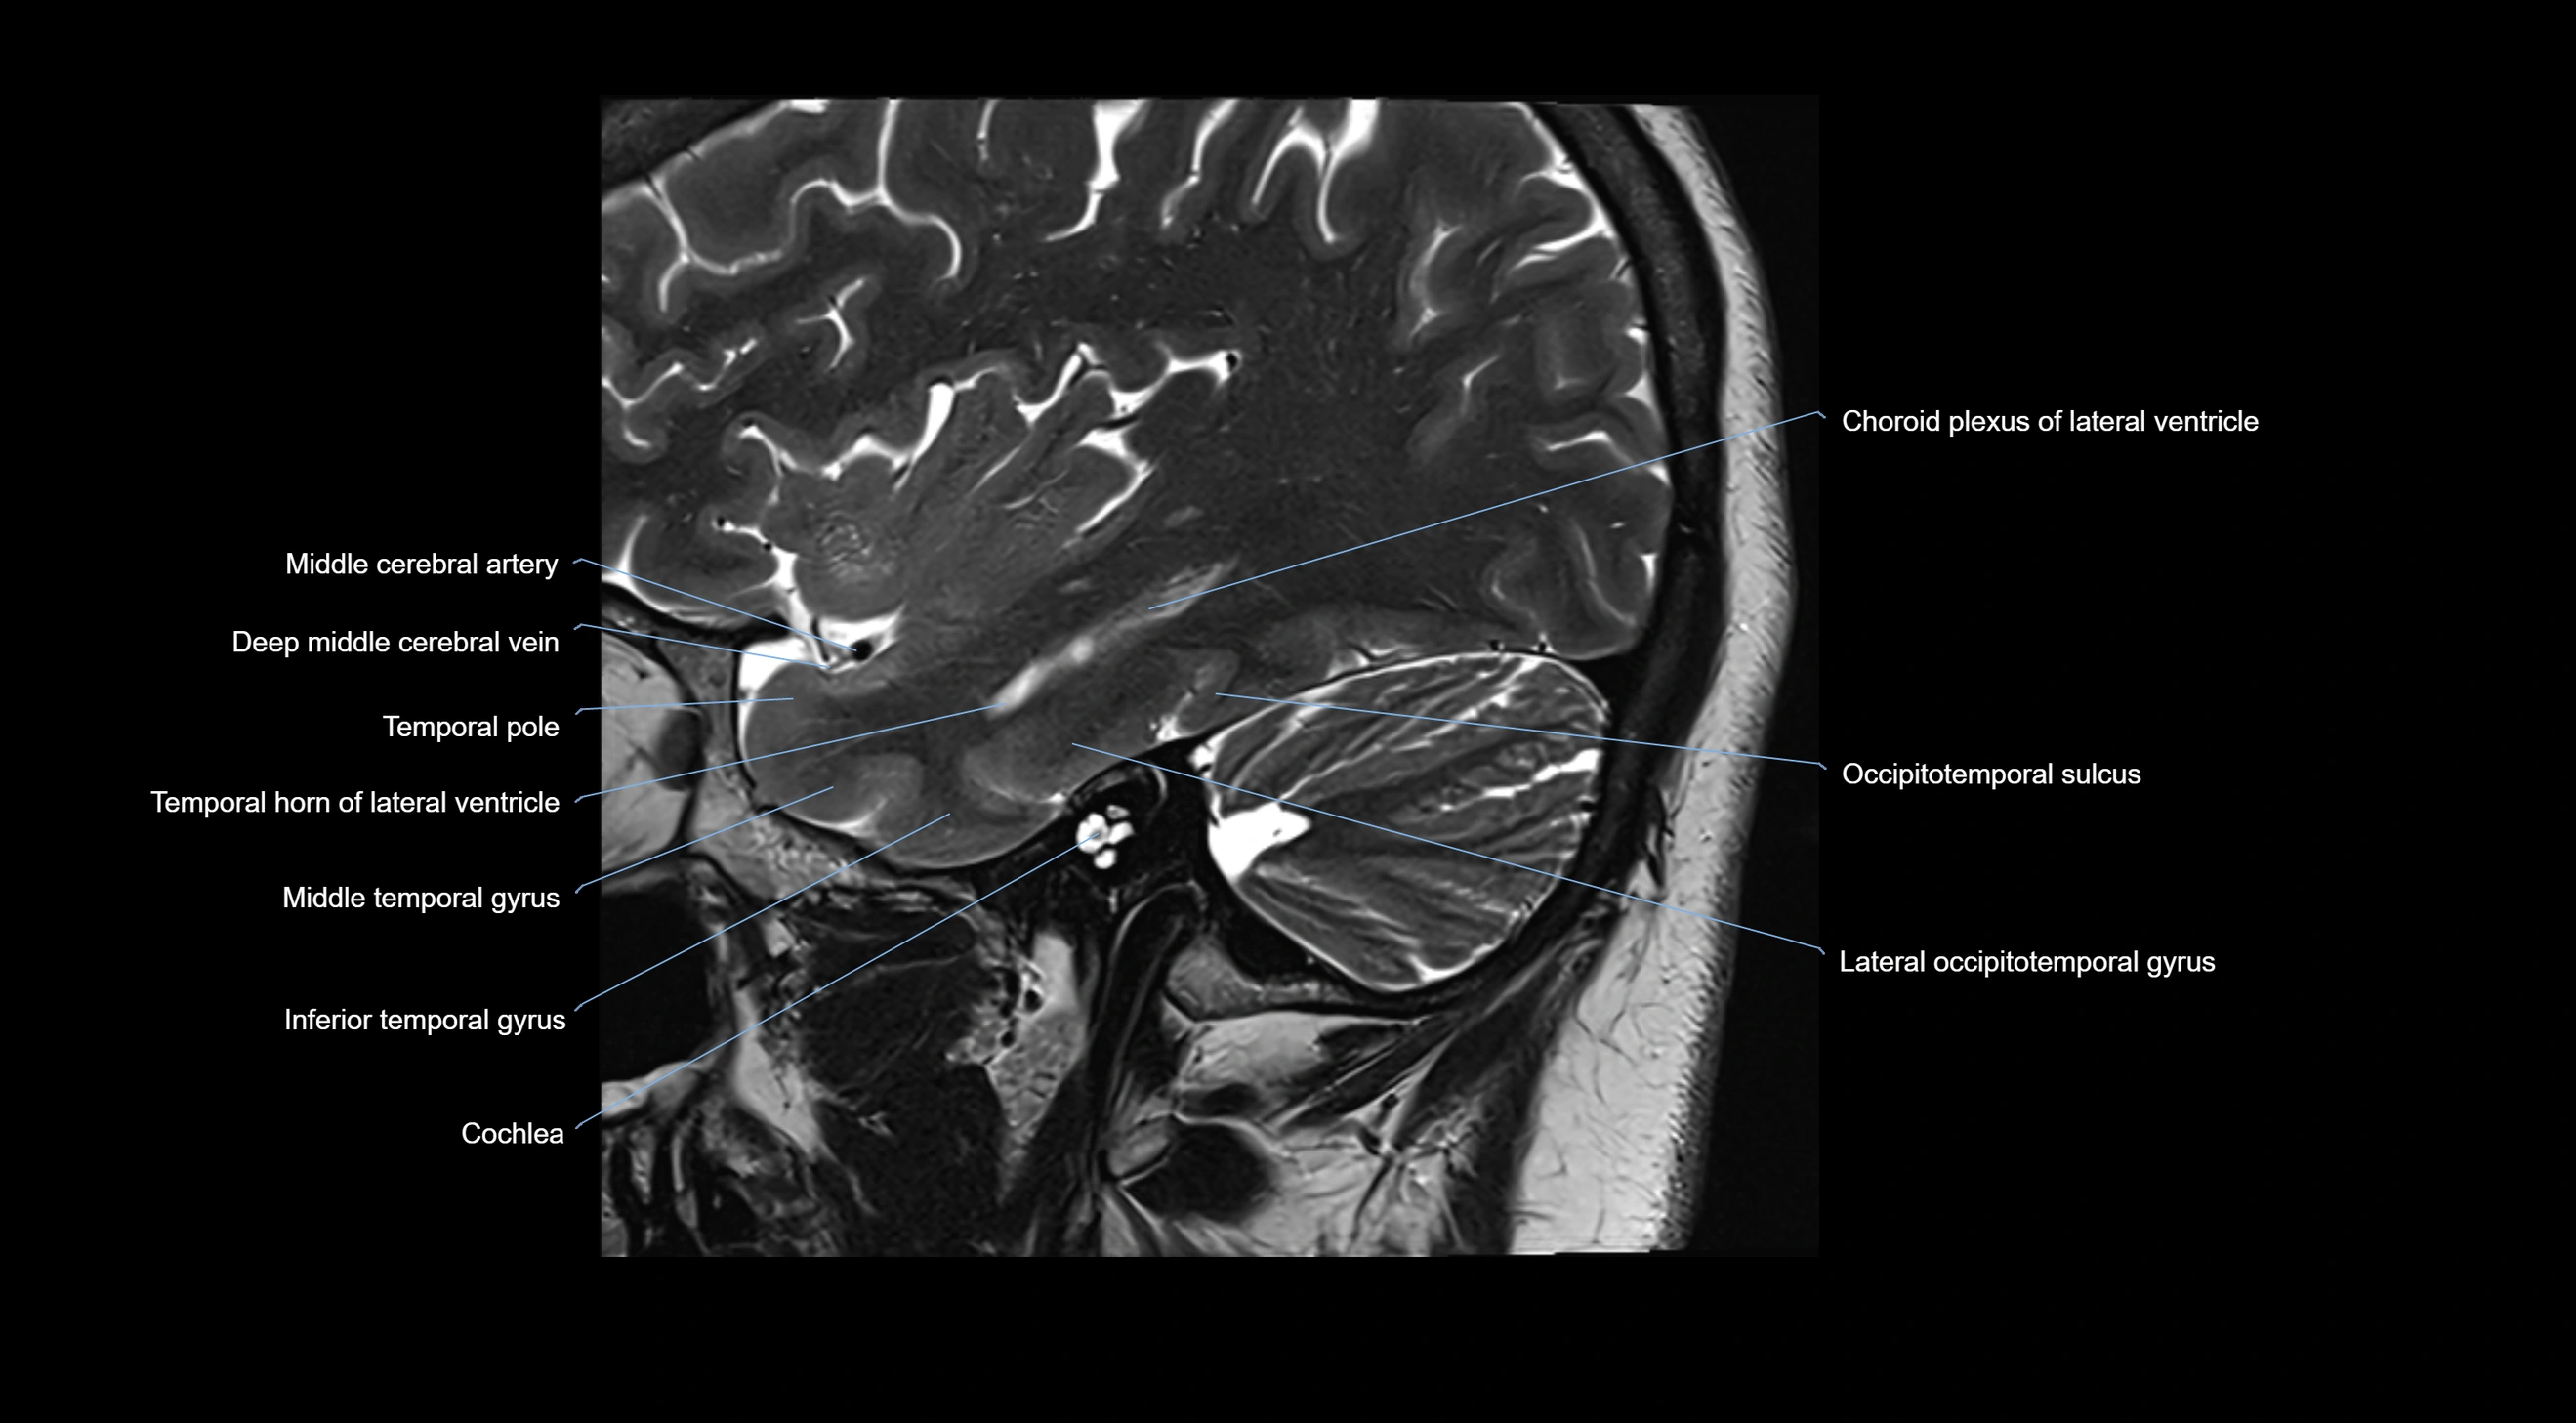

MRI images